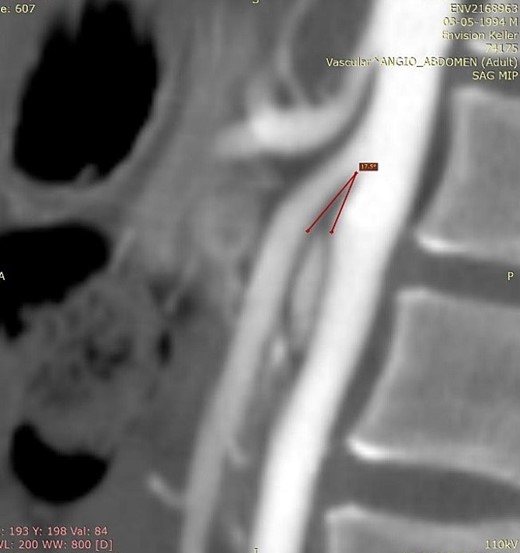

The diagnosis is usually delayed due to lack of knowledge of the disease. Useful diagnostic modalities are computed tomography (CT) as a standard tool, and ultrasonography [3, 6]. CT with mesenteric angiography helps determine the measurement of the aortomesenteric angle, being the main anatomical characteristic of this syndrome the narrowing of the angle between the SMA and the aorta to ≤25°, being the normal 38 to 65° [6, 7]. This narrowing leads to compression of the third portion of the duodenum as it crosses between the aorta and the SMA, and may even result in compression of the left renal vein. The aortomesenteric distance is reduced from the normal 10–28 mm to 2–8 mm, and the severity of the symptoms is related to the aorta – SMA distance [8]. Therefore, an aortomesenteric angle less than 22° and a distance less than 8 mm on contrast-enhanced CT angiography are consistent with SMAS [7].

We present the case of a 21-year-old male patient, with a history of laparoscopic cholecystectomy and 3 cryoablations for Barret’s esophagus with grade III dysplasia, who presented with persistent postprandial vomiting that had caused weight loss of 11 kg in the last 2 years without apparent cause, associated with gastroesophageal reflux that has worsened over time, occasional stabbing abdominal pain in the epigastrium, painful constipation, bloody stools and steatorrhea, managed clinically and symptomatologically without improvement in the condition. On evaluation, the patient was thin, with a BMI of 17.31 kg/m2, and in paraclinics, in endoscopy (Figs 1 and 2), Barret’s esophagus and hiatal hernia; In tomography (Figs 3 and 4), an aortomesenteric angle of 17.5°, with aortomesenteric distance of 4 mm.

Computed tomography. Aortomesenteric distance of 4 mm. Wilkie’s syndrome.